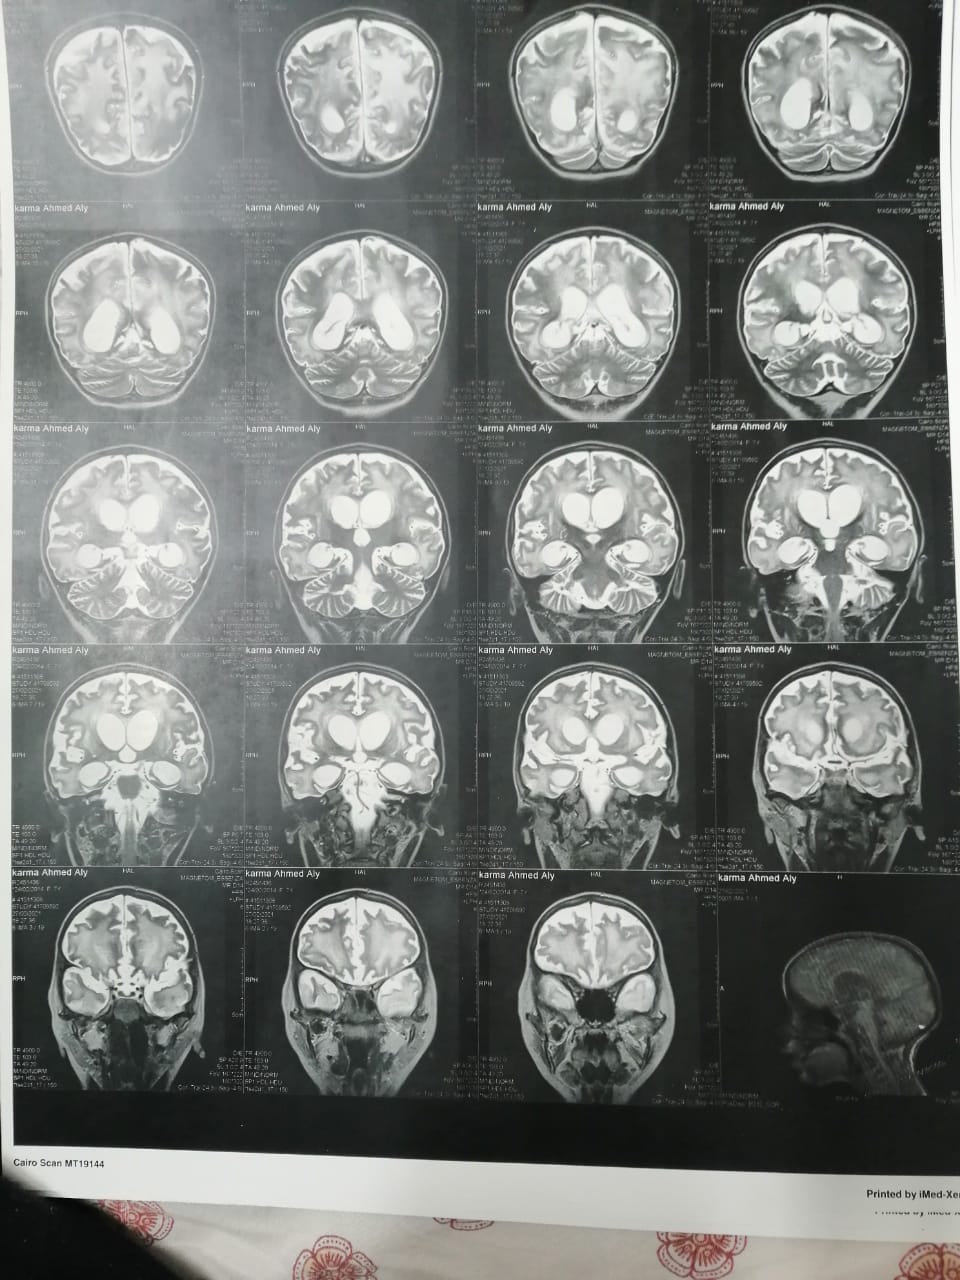

استغاث أحمد علي، بالمسؤولين، لعلاج ابنته صاحبة الـ7 سنوات، المصابة بضمور شديد في المخ، موضحا أن ابنته كانت تعاني من ارتفاع ضغط الشريان الرئوي، وأثناء علاجها أشارت طبيبتها بدواء خاطئ، أدى إلى إصابتها بضمور في المخ.

وأشار إلى أنه بعد خروج كارما من المستشفى تم إجراء فحوصات أخرى عليها، تبينت عدم التطابق بين التقارير الطبية لها بداخل المستشفى والفحوصات الجديدة.

وقال علي: "بنتي جالها ضمور في المخ وفي كل الحواس، بسبب الدوا الغلط، بنعملها علاج طبيعي بيتكلف في الشهر 20 ألف جنيه"، مشددًا": "هي بتفتح عينها بس".